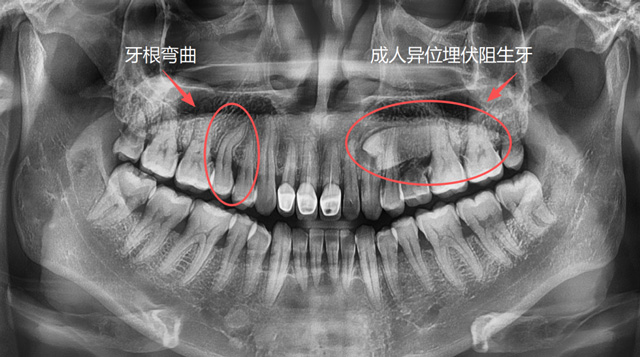

成人牙根弯曲、异位埋伏阻生牙

想要让一颗牙脱位,直的牙根是比较好操作的,弯的牙根因为有一定的弧度,需要顺着这个弧度来解除阻力。如果反着用力,可能会造成牙根折断,取断根需要去骨,就会损失一些牙槽骨的骨量。

为什么有的牙可以完整取出,有的牙需要切割成两三块再取出呢?原因就是因为它们的解剖结构和阻力点不同,拔牙手术的方案也有所差异。

总的来说,医生会根据牙齿的解剖结构和位置等因素去判断阻力,去分析怎么把这个阻力解除,再采用相应的手术方案和工具来完成手术。